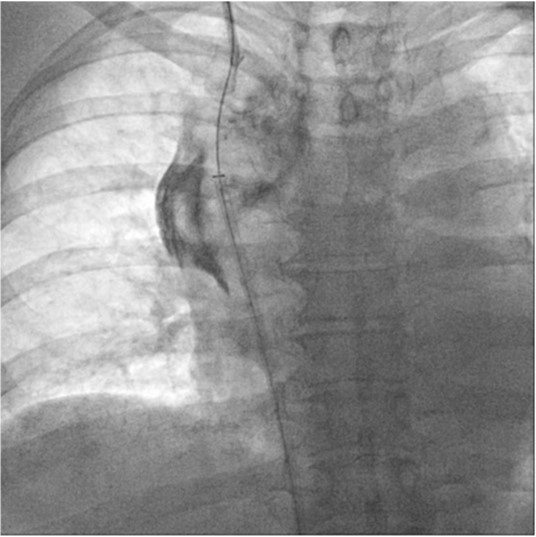

Fig. 4.

Fig 4. Fluoroscopic image shows Colapinto needle punctured the right superior vena cava across the obstructed segment. The tip of the needle is facing back side of the body (long arrow). Confined contrast leakage is noted around the obstructed right brachiocephalic vein (small arrows).

초음파 유도 하에 우측 팔의 동정맥루 graft를 천자한 후 정맥조영술을 시행하여 우측 상완두정맥의 폐색을 확인함(Fig. 1). 5Fr Cobra 카테터(Cook, Bloomington, IN, USA)와 친수성 0.035 inch 유도철사(Terumo, Tokyo, Japan)로 폐색부위의 통과를 시도하였으나 실패함. 우측 대퇴정맥을 천자하고9Fr 65cm sheath (Arrow, Deutschland, Erding, Germany)를 상대정맥까지 진입시킨 후 5Fr Davis 카테터를 통해 약 2cm 길이의 상완두정맥 폐색 부위를 확인함(Fig. 2). Davis 카테터와유도철사로 상대정맥에서 우측 상완두정맥으로 통과를 시도함. 유도철사의 soft tip 부분으로 시도하였을 때 통과가 되지 않아서 반대쪽 hard tip 부분으로도 통과를 시도 하였으나 실패함(Fig.3). 유도 철사의 soft tip 과 hard tip 양쪽 모두 사용 하여 통과를 시도하였으나 막힌 부위의 위쪽 부분은 앞쪽(anterior side of the body) 을 향하고 있고 아래쪽 부분은 뒤쪽(posterior side of the body)를 향하고 있어서 천자 방향을 맞추기 어려웠음(Fig. 3). 우측 내경정맥을 천자하고 5Fr sheath를 삽입함. Sheath를 통해서 5FrKumpe 카테터와 0.035 inch 유도철사로 위에서 아래 방향으로 폐색부위 통과를 시도함. Hard tip으로 시술 도중 폐색혈관 주위로 유도 철사가 천자되어서 조영제의 누출이 있었으나 천자부위 주에 국한되어 있었고 임상적으로 문제 있는 혈류역학적 변화는 오지 않았음. Kumpe 카테터와 유도철사로는 천자 방향을 맞추기가 어려워서TIPS set (Cook, Bjaeverskov, Denmark)를 사용하기로 함. 천자된내 경정맥에 10Fr introducer sheath를 삽입하고 20G Colapinto needle을 폐색부위까지 진입시킴. 양쪽에서 정맥 조영술을 시행하여 폐색된 부위의 위치와 길이를 여러 각도에서 정확히 파악한 후, 폐색 부위를 천자함(Fig. 4). 천자 후 Colapinto needle을 통해 유도철사를 상대정맥에 진입시킴. 대퇴동맥을 통하여 삽입된 snare 카테터(ev3, Plymouth, MA, USA)를 이용하여 대퇴정맥 밖으로 유도철사를 빼냄(through and through technique)(Fig 5). 유도 철사만 통과된 상태에서 천자부 주위에 여러번의 천자로 인한 조영제 누출이 있었으나 주출된 조영제의 양이 적었으며 천자부 주위에 국한되어 있었음. Tractogram시행시 조영제의 누출은 보이지 않아서 유도 철사 주위에 국한 되어 있어서 풍선확장술을 시행 하기로 함(Fig. 6).대퇴 정맥을 통해 유도철사를 0.035 inch Amplatz wire(Cook, Bjaeverskov, Denmark)로 교체하여 내경정맥까지 진입시킨 후 풍선카테터 (Bard, NJ, US)를 삽입함.천자된 통로를 따라 직경 6 mm에서부터 16 mm까지의 풍선카테터로 차례대로 풍선확장술을 시행함(Fig. 7). 시술 후 정맥조영술에서 폐색부위는 개통되어 원활한 혈류를 보였음(Fig. 8). 시술 후에 오른쪽 팔의 종창은 호전됨.